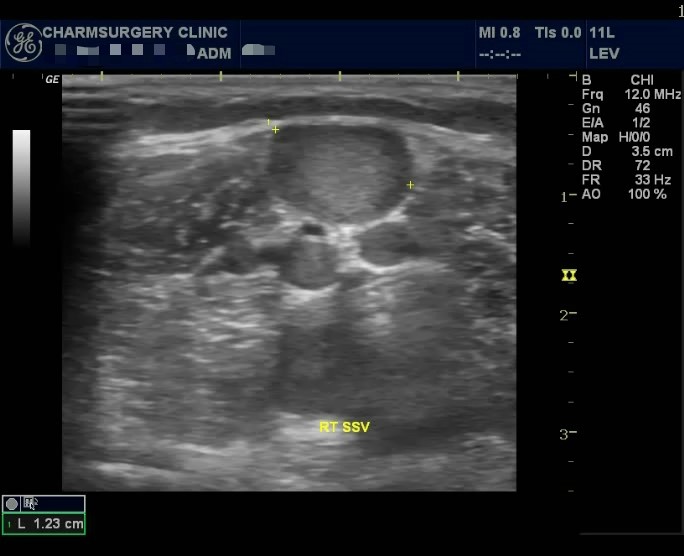

하지만 혈관초음파 검사 결과상

혈관의 확장 및 역류 소견이 관찰되고 있는 수술적응증에 해당되는 소견이었습니다